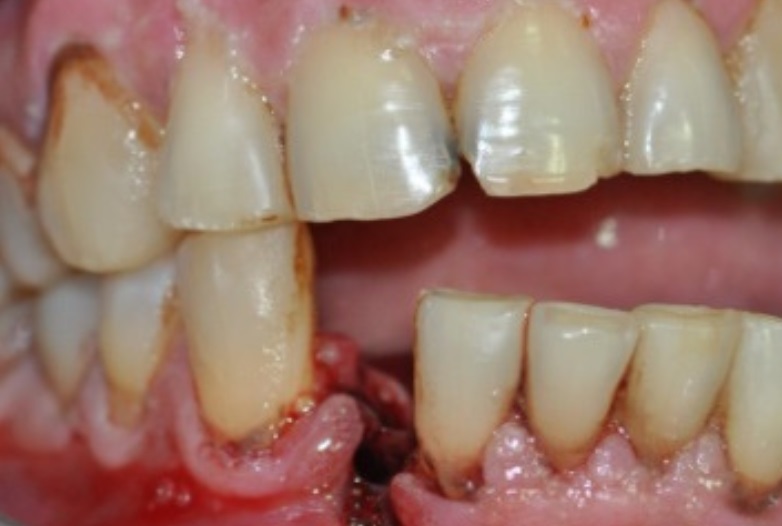

Tooth is Displaced back, forward, or down.

- Try to push back into the correct position. Biting into a folded or balled up towel can help push it back.

- See the dentist ASAP.